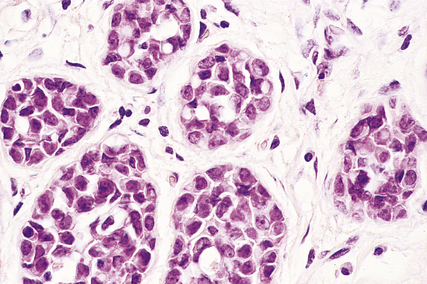

Histologically, the tumour cells are arranged in groups, cords and gland-like structures. Quite marked variations can be seen between different carcinomas even though they are of the same type (Fig. 18.22). For example, the size of the solid groups of cells can be variable, and ductal carcinoma in situ is often present. The amount of stroma between the tumour cells can also vary, but in those carcinomas in which it is prominent it is most marked at the centre, with the periphery being more cellular. Collections of elastic tissue (elastosis) around ducts or within the stroma are common in tumours with a scirrhous reaction.

image

Fig. 18.22 Infiltrating ductal carcinoma. The lesion is composed of irregular solid groups of cells in a dense fibrous stroma, with an associated lymphocytic infiltrate.

The degree of differentiation or grade of the tumour is based on the extent to which it resembles non-tumorous breast: whether the cells are in a gland-like pattern or as solid sheets; the degree of nuclear pleomorphism; and the number of mitotic figures present. A well-differentiated (grade I) infiltrating duct carcinoma tends to behave less aggressively than a poorly differentiated (grade III) tumour, which is composed of sheets of pleomorphic cells with large numbers of mitotic figures.